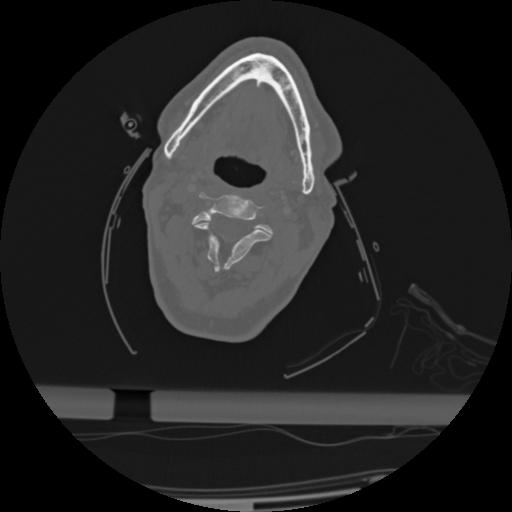

22 ANGIO,CE,Vol,0.5,ANGIO,,